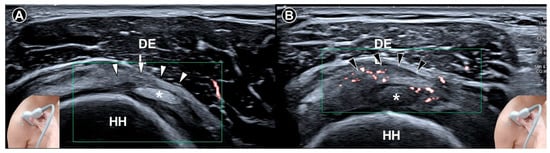

Four characteristic sonographic features were identified: coracohumeral ligament thickening (defined as a threshold of 3.0 mm) (Figure 1), inferior capsule thickening (cutoff values ranging from 2.0 mm to 3.5 mm) (Figure 2), rotator interval abnormalities (hypoechoic soft tissue thickening and/or increased vascularity) (Figure 3), and restriction of the range of motion. Their respective sensitivities were 64.4% (95% CI: 48.8–78.1), 82.1% (95% CI: 73.8–88.7), 82.6% (95% CI: 74.1–89.2), and 94.3% (95% CI: 84.3–98.8), while specificities were 88.9% (95% CI: 76.0–96.3), 95.7% (95% CI: 90.3–98.6), 93.9% (95% CI: 89.8–96.7), and 90.9% (95% CI: 75.7–98.1), respectively. The restriction of the range of motion will be further elaborated in the section on Dynamic Examination. These findings support the incorporation of B-mode ultrasound into routine diagnostic workflows for adhesive capsulitis, particularly in settings where magnetic resonance imaging is less accessible or cost-prohibitive.

Homsi et al. [19] included 17 arthrography-confirmed adhesive capsulitis cases among a cohort of 306 patients and found that mean coracohumeral ligament thickness measured by ultrasound was notably elevated at 3 mm in affected shoulders, compared to 1.34 mm in asymptomatic shoulders and 1.39 mm in other painful shoulders (all p < 0.05). This early evidence underpins the use of coracohumeral ligament thickening as a sonographic hallmark of the condition.

Figure 1. Ultrasound imaging of the coracohumeral ligament (white arrowheads) in a normal shoulder demonstrates a clear intra-ligamentous fibrillar pattern (A). In contrast, ultrasound imaging of the coracohumeral ligament (black arrowheads) in a shoulder with adhesive capsulitis shows thickening and loss of the intra-ligamentous fibrillar architecture (B). DEL, deltoid muscle; COR, coracoid process; HH, humeral head.